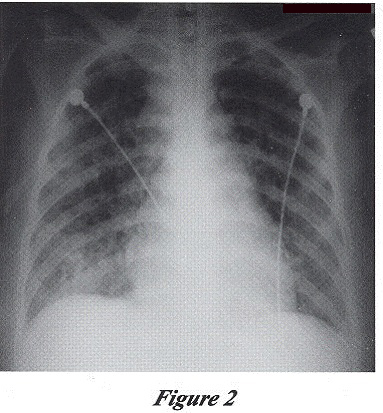

She had persistent fever and developed Type 1 respiratory failure despite having received intravenous Cefuroxime for five days. Repeated CXR showed deteriorating diffuse lung shadows (Figure 2). Clarithromycin and empirical anti-TB drugs including Isoniazid 300 mg QD, Rifampicin 450 mg QD, Ethambutol 1250 mg QD and Pyrazinamide 1500 mg QD were started. Sputum for AFB smear was positive and subsequent culture confirmed Mycobacterium tuberculosis with favourable sensitivity pattern. Fine needle aspiration of the left supraclavicular lymph node was performed and culture of the aspirate also showed Mycobacterium tuberculosis with favourable sensitivity pattern. Anti-HIV serology was positive, CD4 count was 32/mm3, CD8 count was 230/mm3 and HIV viral load was 139xlOOOcopies/ml.